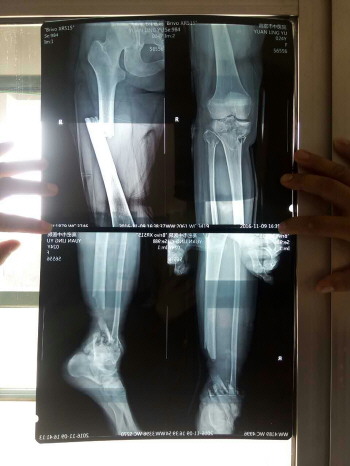

袁玲玉的双腿骨折相当严重。

袁玲玉膝盖以下右腿已被截肢。

袁玲玉被紧急送到高密市中医院,并请解放军第八十九医院的骨科专家会诊。经检查发现,袁玲玉左侧肺部破裂,左脚粉碎性骨折,右腿多处骨折,最严重的是盆骨多处骨折并造成大量内出血,情况十分危险。为了保住袁玲玉的生命,医院首先对其肺部和盆骨内的出血进行处理。经过抢救,袁玲玉脱离了生命危险,可是当医生对其腿部进行治疗时,发现袁玲玉的右腿不仅多处骨折,而且多处血管破裂,由于错过了最佳治疗时间,血管已经坏死,有进一步危害其生命的可能,无奈之下,于11月10晚对袁玲玉膝盖以下的右腿进行了截肢手术。